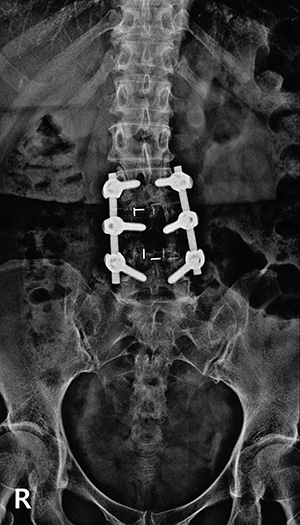

▼ 척추뼈 2개를 묶은 유합술 ▼

• 유합술 전면 X-ray

• 유합술 측면 X-ray

▼ 척추뼈 3개를 묶은 유합술 ▼